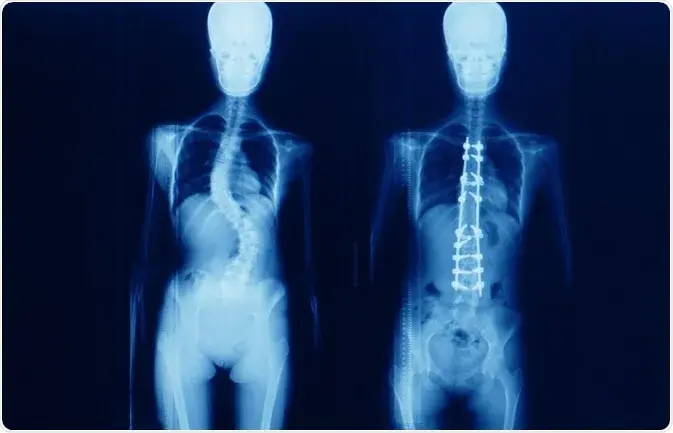

Technically, Scoliosis is an abnormal lateral (side) curvature of the spine. This occurs more commonly in teenage females. However, it is difficult to notice this problem until one may have uneven shoulders or hips due to the spine’s curve. Sometimes, scoliosis can be due to birth deformity or neuromuscular disorders like cerebral palsy.

- X-ray

Surgery is also recommended for a patient if he/she has a curve greater than 45 to 50 degrees, as it may affect lung function. The best age group to perform Scoliosis surgery in India is between 3 and 10 years when the child is still in the growing phase, as the curve tends to increase during the growth period. Surgery can also be performed on adults suffering from severe pain.